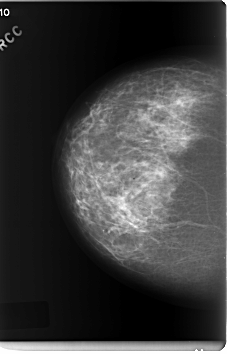

C_0207_1.RIGHT_CC

RIGHT_CC LINES 6008 PIXELS_PER_LINE 3848 BITS_PER_PIXEL 12 RESOLUTION 50 NON_OVERLAY